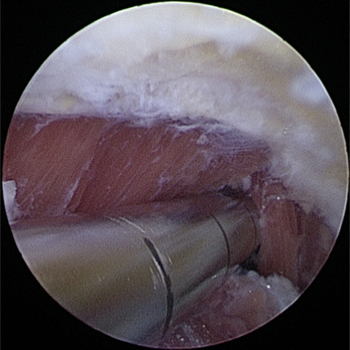

관절내시경을 통해 자라난 뼈 조각과 관절 내 유리체를 제거하며

자라난 골극을 제거해준 모습